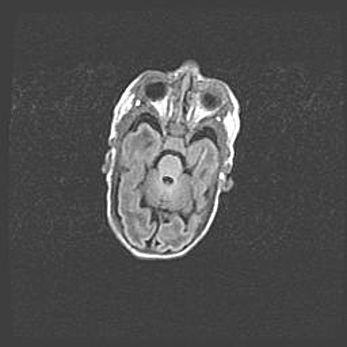

Церебральная ишемия II.

Возраст: 5 дней

Вес: 3400 г

Пол: женский

Окружность головы: 35 см

Срок гестации: 39 недель

Церебральная ишемия – это заболевание, характеризующееся недостаточностью (гипоксией) либо полным прекращением (аноксией) снабжения мозга кислородом по причине закупорки одного или нескольких сосудов. Это приводит к  что метаболическим расстройствам различной степени тяжести в тканях головного мозга, развитию коагуляционных некрозов и гибели нейронов.